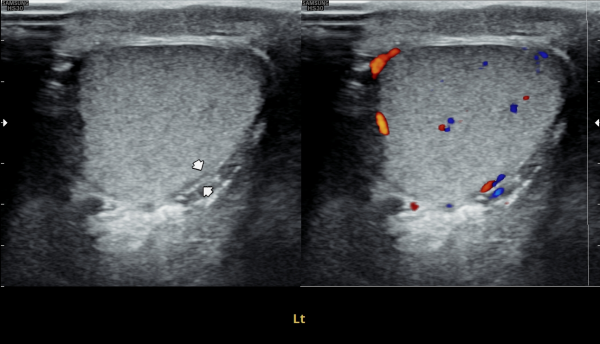

첫 내원 당일 검사한 고환의 초음파 사진상 앉아서 생활하는 직업상 고환 동맥의 순환 장애로 죽상동맥경화증의 소견을 보여 식이요법과 운동요법을 말씀드리고 정관의 표적 치료를 시작한 사진입니다.

On the day of your first visit, the testicular ultrasound showed signs of reduced blood flow in the testicular artery, likely from long hours of sitting. This may have caused early signs of atherosclerosis. We discussed healthy lifestyle changes, including diet and exercise, and started targeted treatment for the vas deferens.

4개월 동안 정관의 표적 치료와 직장 생활중 장시간 앉은 업무를 개선하여 운동을 겸한후 추적 고환의 초음파 사진장

고환동맥의 축상경화증 소견이 치료되고 있는 사진입니다.

This follow-up scrotal ultrasound image, taken after four months of targeted treatment for the vas deferens and lifestyle improvements including reduced prolonged sitting during office work and regular exercise, shows improvement in axial arteriosclerosis of the testicular artery.